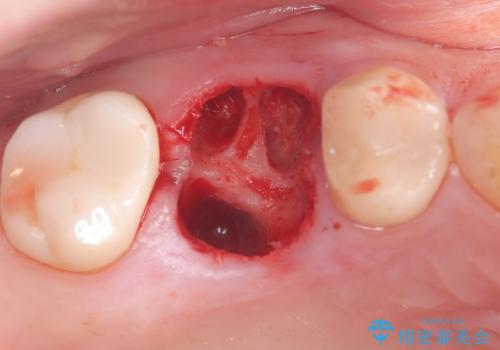

- 右上の6番の奥歯の痛みを主訴に来院されました。精密検査の結果、根管内を歯科用顕微鏡で確認したところ、肉眼では見えないクラック(ひび割れ)が発見されました。このクラックが痛みの原因であり、将来的に歯の保存が難しいと判断。患者様と話し合い、歯を残すことを諦め、抜歯と同時にインプラントを埋入する抜歯即時埋入インプラントによる治療計画を立案しました。これにより、治療期間と身体への負担を最小限に抑え、確実な解決を目指しました。

今回の治療では、まず原因となっていた奥歯を慎重に抜歯し、その直後にインプラントを埋入しました。この抜歯即時埋入により、抜歯からインプラント埋入までの期間を省き、骨の吸収を最小限に抑えられました。治療後は痛みや腫れも少なく、患者様は快適に過ごしていただけました。最終的に、わずか3ヶ月でセラミッククラウンを装着。機能性と審美性を兼ね備えた新しい歯により、長年の痛みが解消され、快適な食生活を取り戻していただけました。